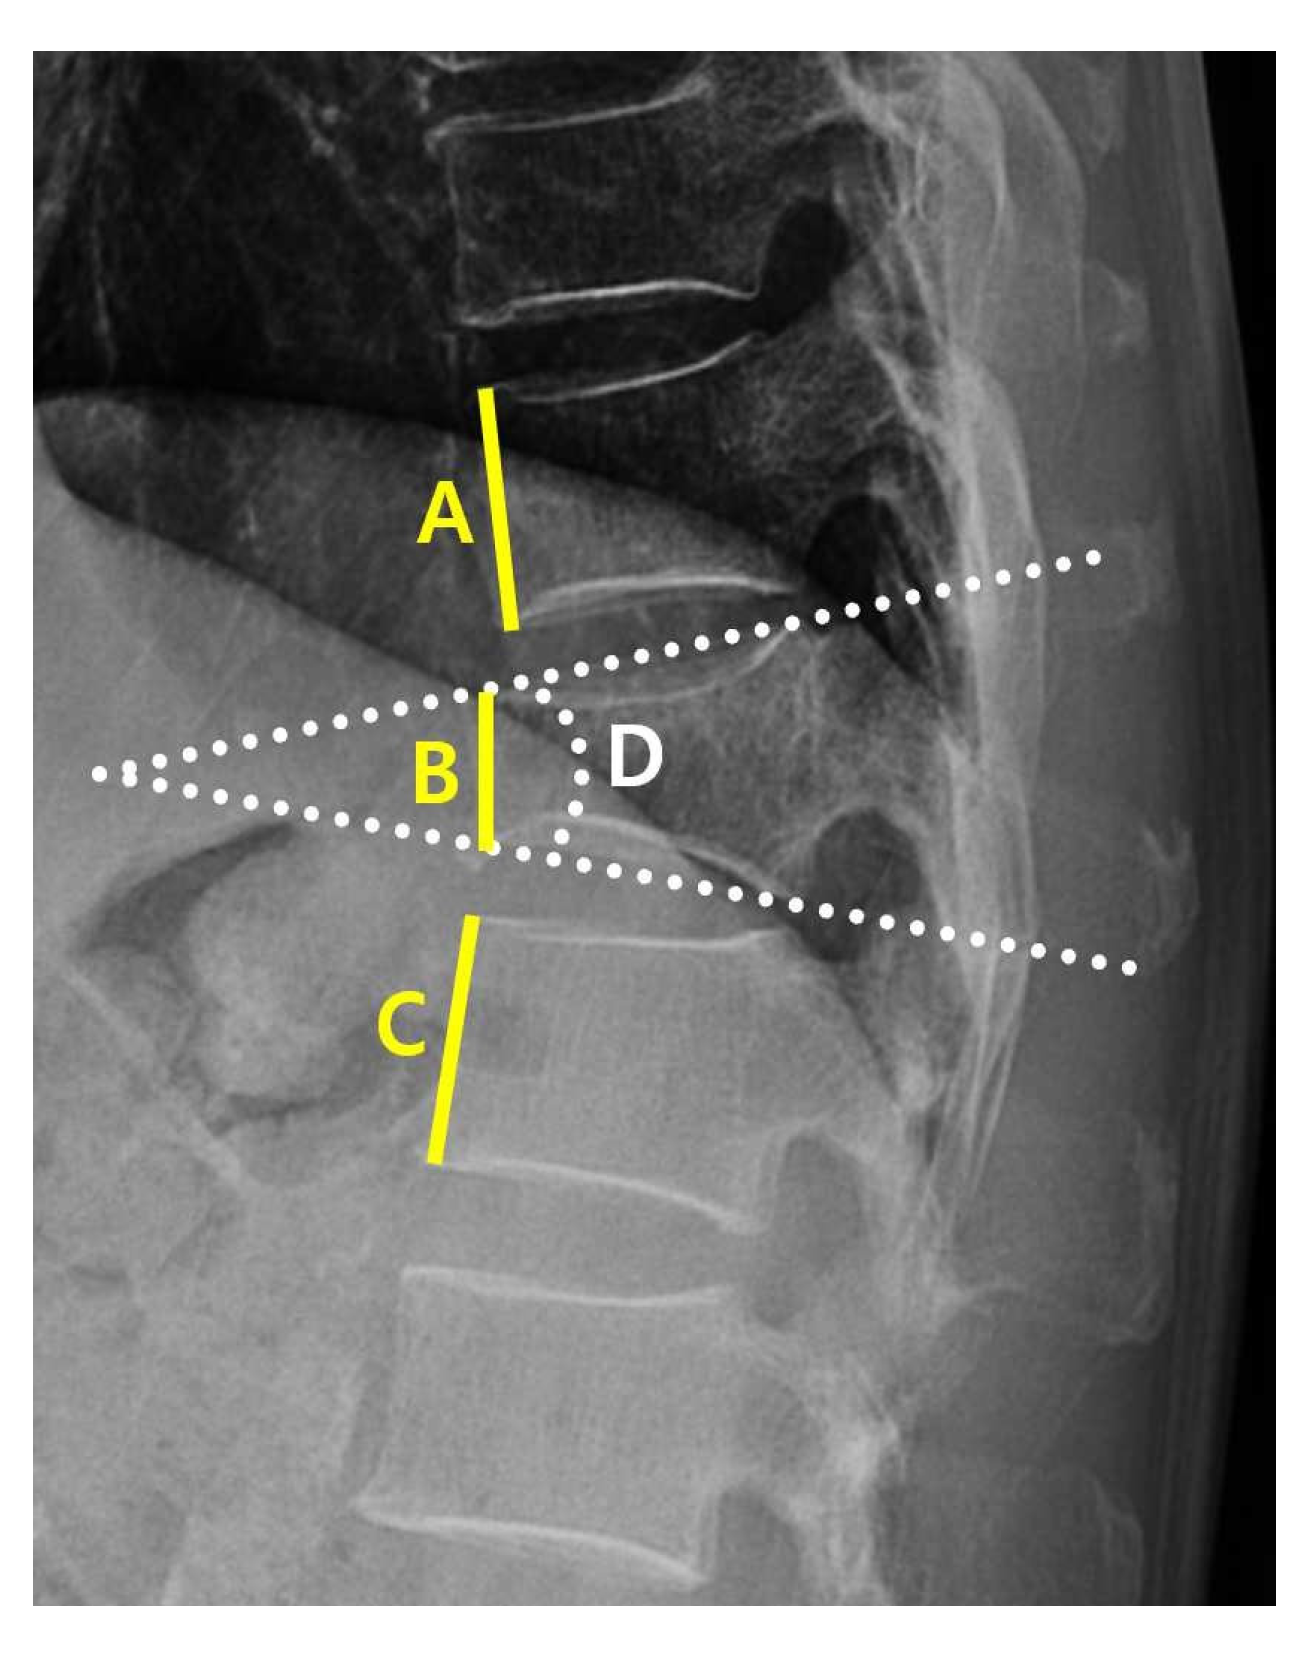

2.3. Data Collection

| PR (lateral view) | Kyphotic angle (°) | 19.89 ± 0.49 | 25.01 ± 4.21 | Kyphotic angulation at VCF | <0.05 * |

| Compression Value | 34.41 ± 1.27 | 48.31 ± 6.50 | Compression ratio at VCF | <0.05 * | |

| MRI (axial view) | Disc (cm/m2) | 12.51 ± 0.21 | 15.14 ± 0.93 | CSA of endplate at VCF | <0.05 * |